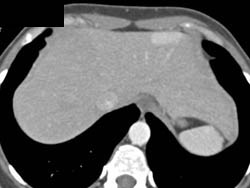

Renal Cell Carcinoma With Liver Metastases